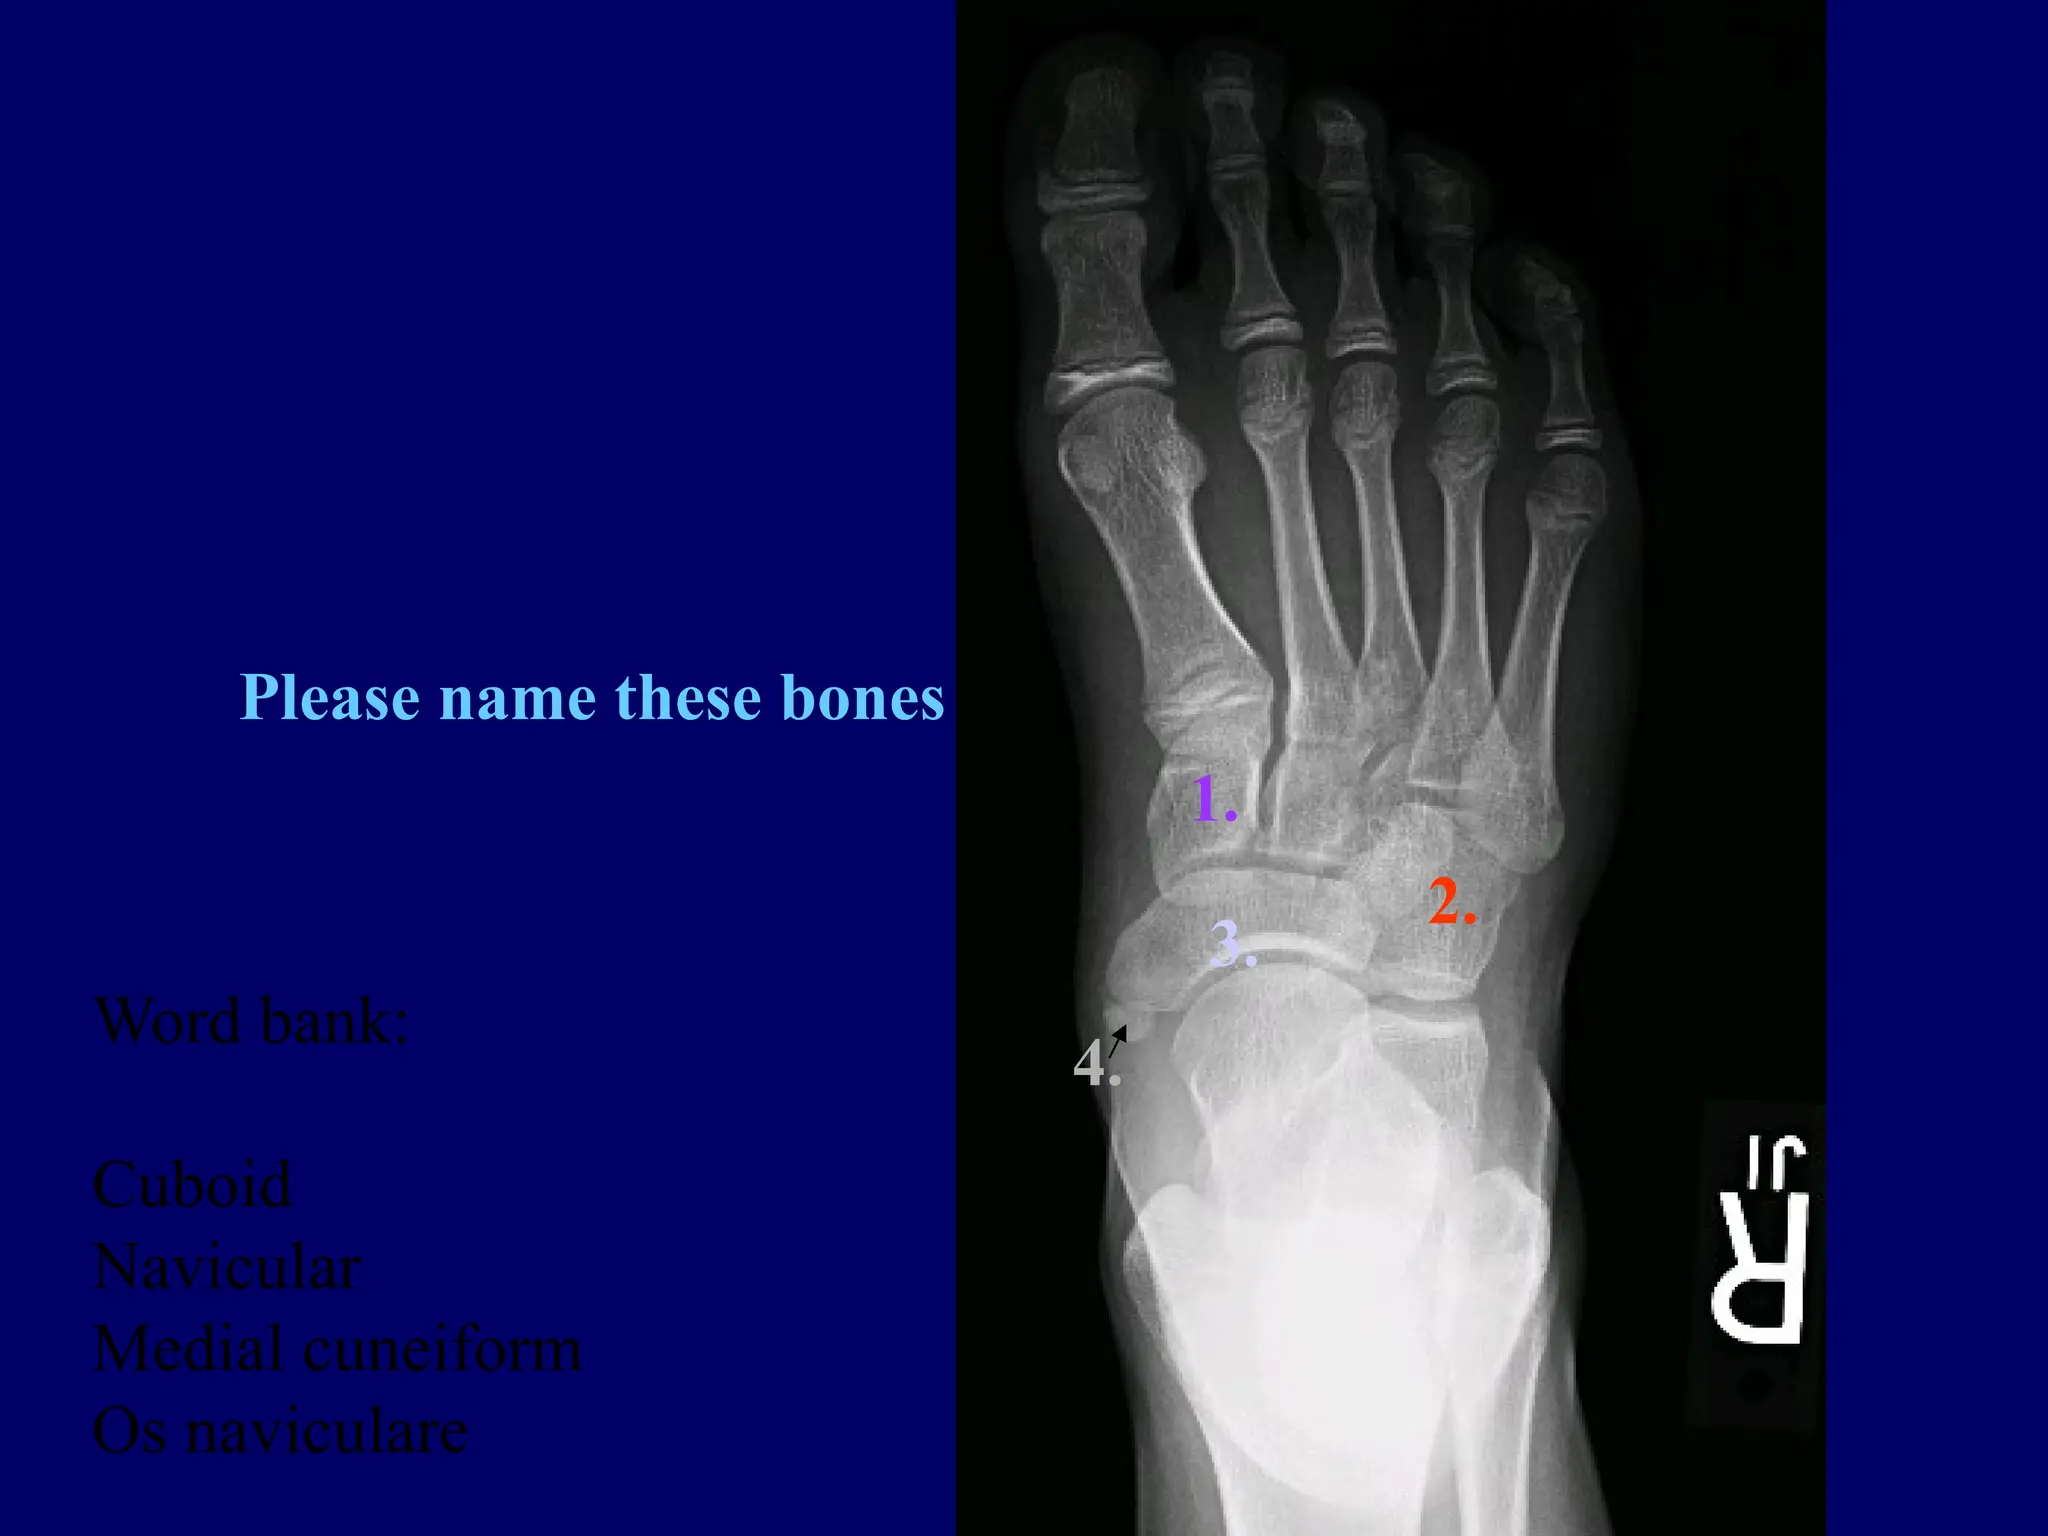

History: 11 y/o twisting

injury of the foot

Please name these bones

Word bank:

Cuboid

Navicular

Medial cuneiform

Os naviculare

History: 11 y/otwisting injury of the foot

1. 2. 3. 4. Please name thesebones Word bank: Cuboid Navicular Medial cuneiform Os naviculare